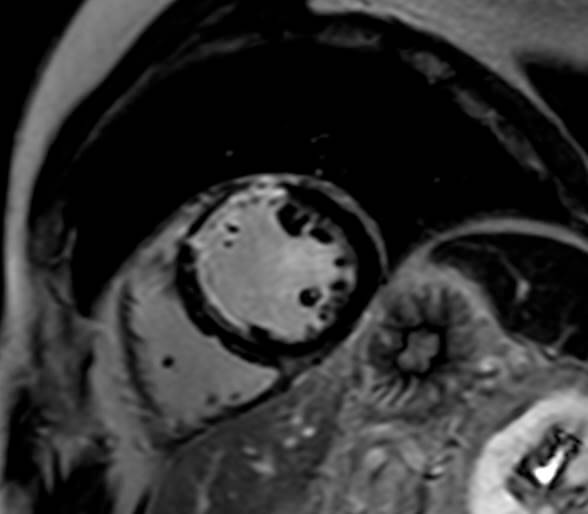

Μαγνητική Τομογραφία Καρδιάς

Η μαγνητική τομογραφία καρδιάς χρησιμοποιείται για τη διάγνωση ποικίλων καρδιακών νοσημάτων, όπως βαλβιδοπάθειες, συγγενείς καρδιοπάθειες, καρδιομυοπάθειες, όγκοι καρδιάς, στεφανιαία νόσος και νοσήματα περικαρδίου.